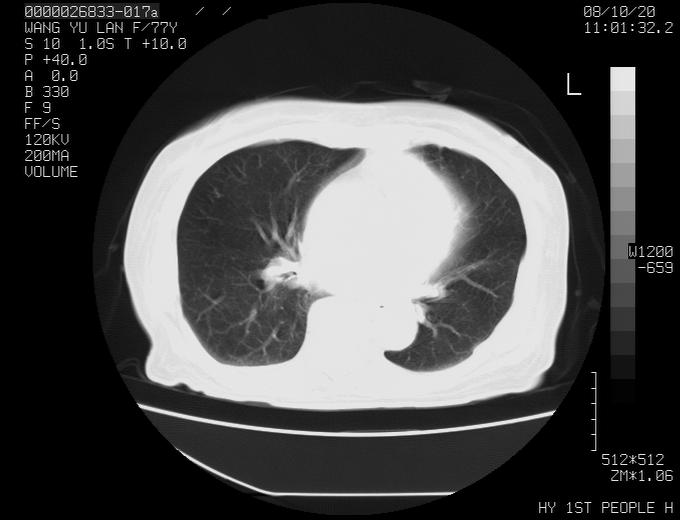

女性,77岁,胸部疼痛半月。左上肺团块影,本人考虑血管畸形,请分析

考虑肺癌

q我认为这么大的年齡,考虑周围型肺ca可能性大

考虑周围型肺ca可能性大

纵隔有多个淋巴结肿大,提示周围型肺癌并转移可能性大。

左肺周围型肺癌并肺门淋巴结转移,很典型了!